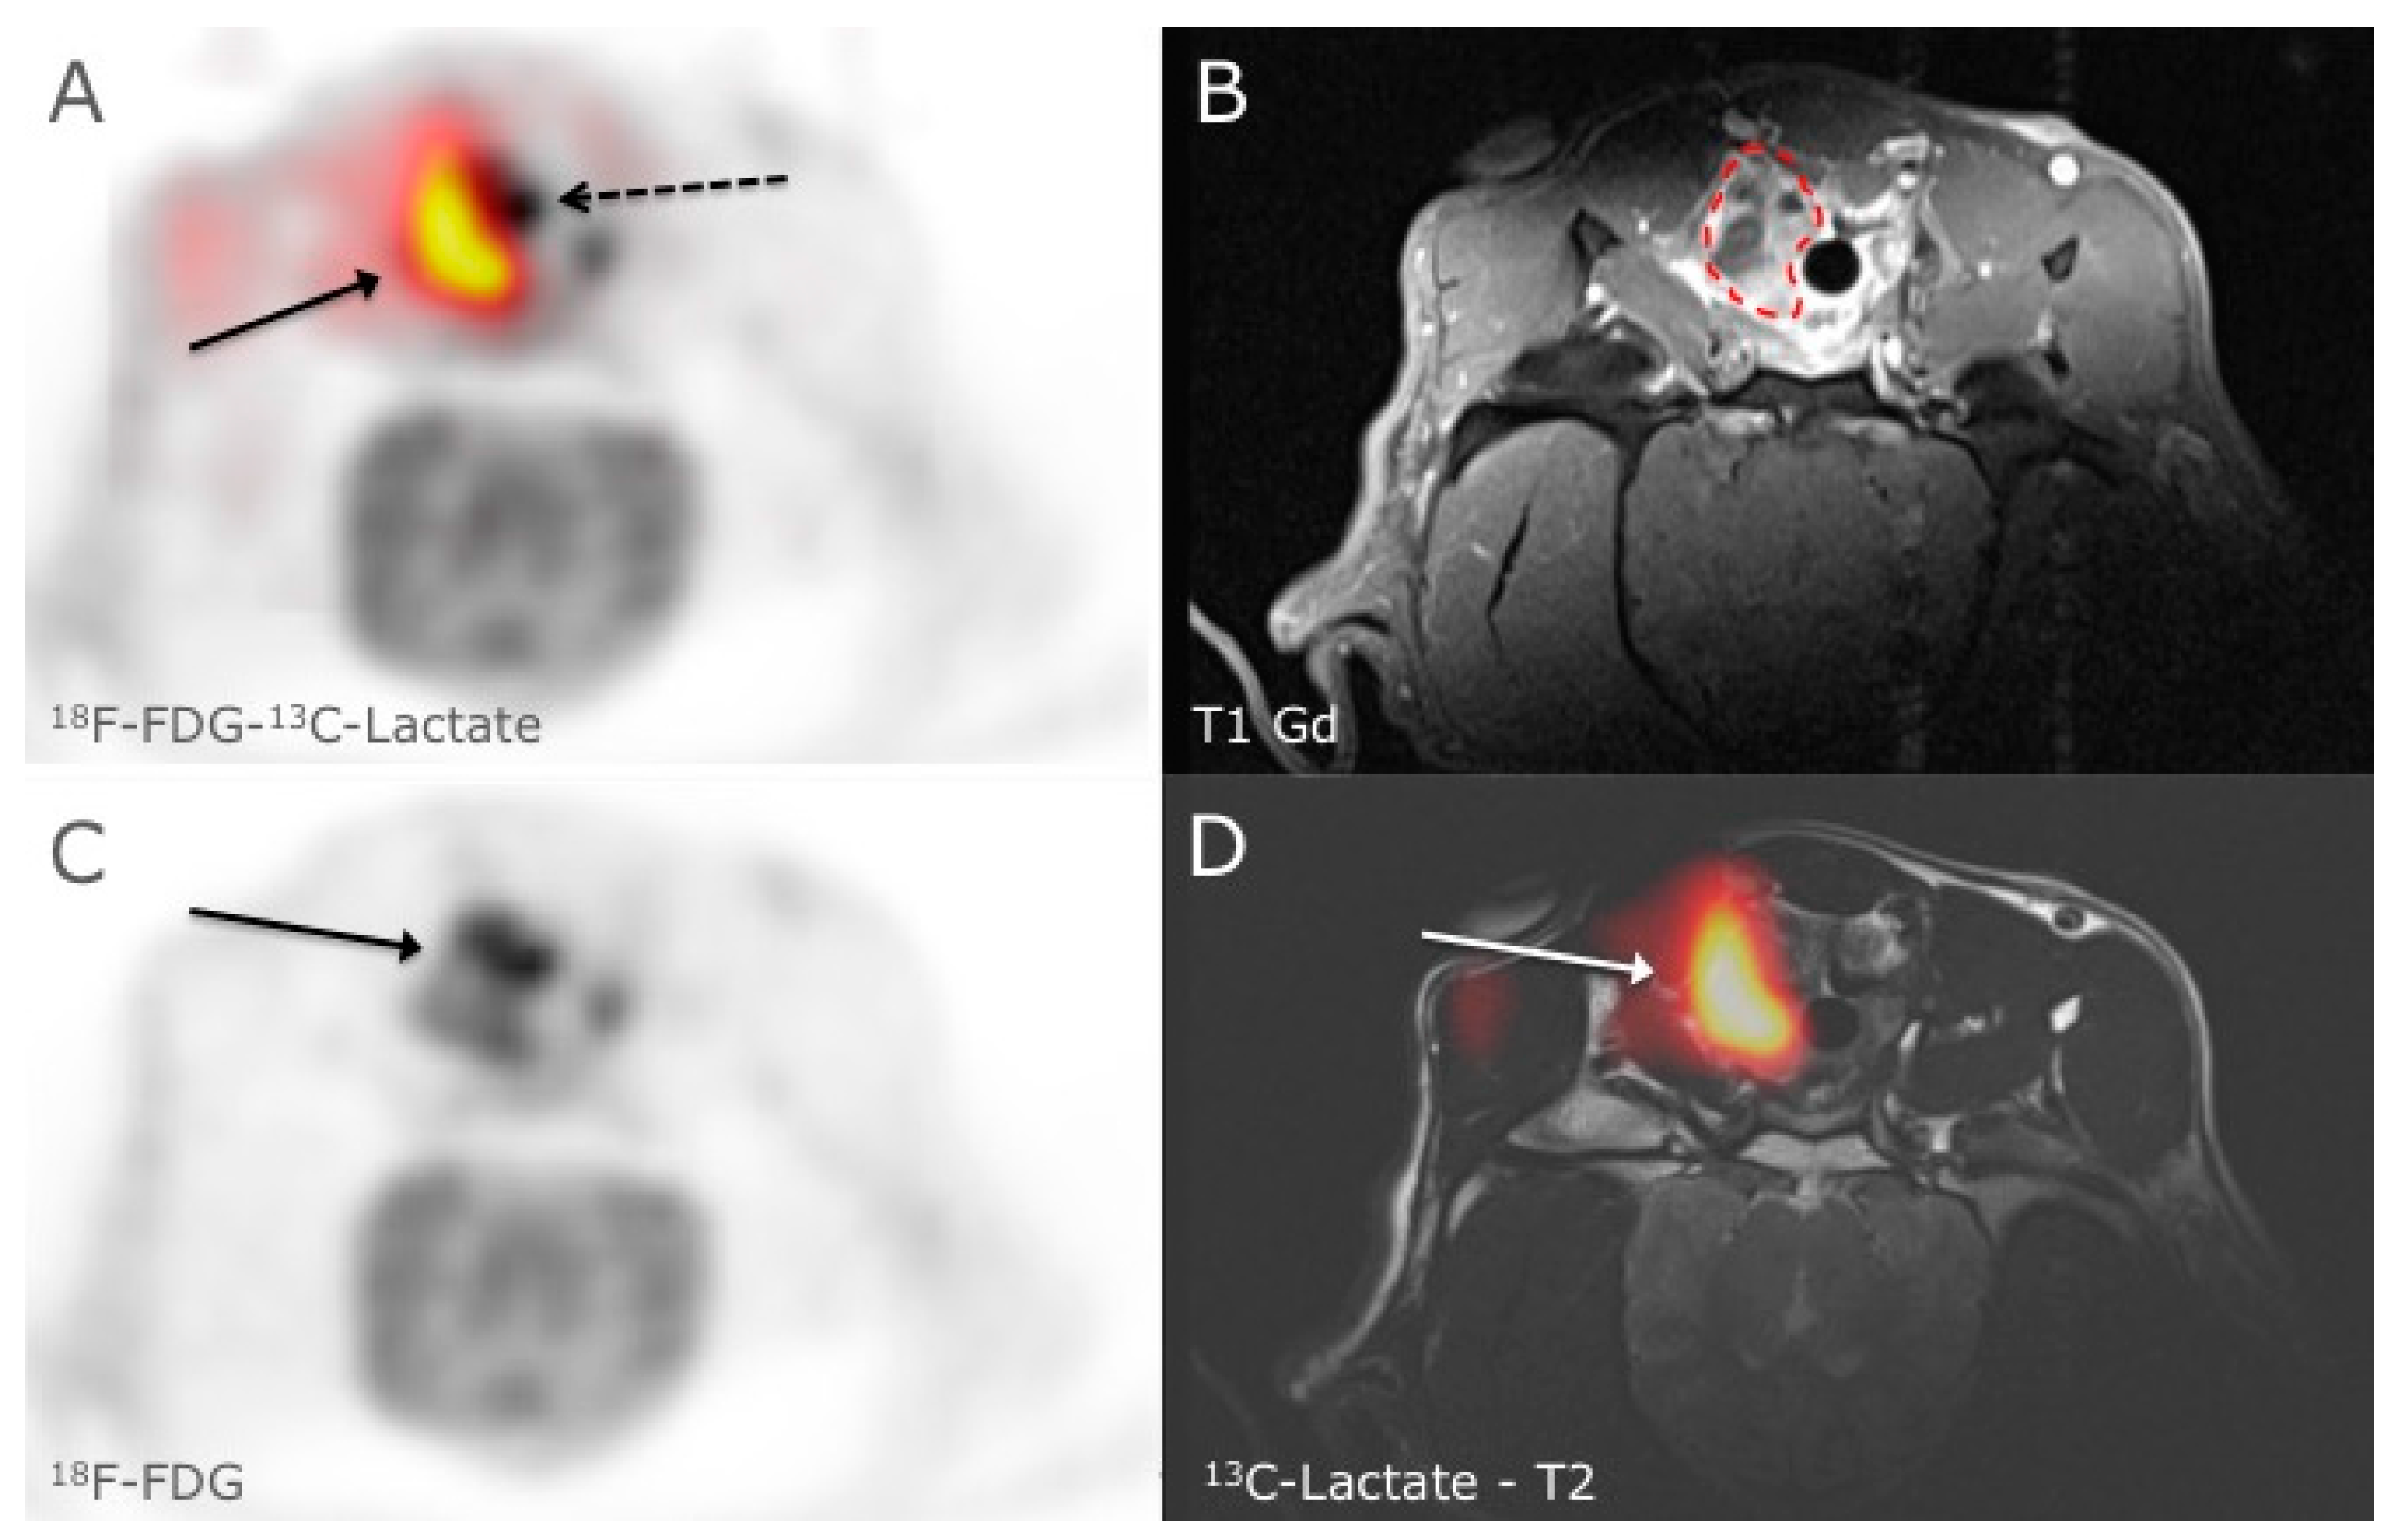

In Vivo Phenotyping of Tumor Metabolism in a Canine Cancer Patient with Simultaneous 18F-FDG-PET and Hyperpolarized 13C-Pyruvate Magnetic Resonance Spectroscopic Imaging (hyperPET): Mismatch Demonstrates that FDG may not Always Reflect the Warburg Effect